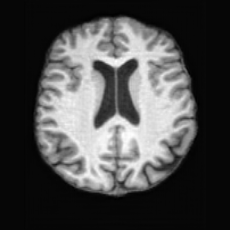

Unconditional Generation. Fig. 4 (a) presents examples of paired lesion masks and brain images generated by USB. Notably, although the paired lesion-brain generation begins unconditionally from random noise, USB produces lesion masks exhibiting diverse locations, sizes, and shapes, while simultaneously generating anatomically coherent brain images with embedded pathological patterns that spatially correspond to the generated lesions within each pair.

In Tab. 1, we present the first quantitative benchmark evaluation of both generation tasks. For the unconditional generation task, we generated 256 paired lesion–brain samples for each lesion type (stroke and WMH). For the conditional generation task, we used masks from the ATLAS and ISLES test sets as stroke lesions, and masks from the ADNI test set as WMH lesions. Notably, for each lesion type, the unconditional generation achieved superior quantitative performance, highlighting that the paired diffusion mechanism effectively generates coherent lesion-brain pairs through joint modeling between USBbrain and USBlesion. Additional generation results are provided in Suppl. A.